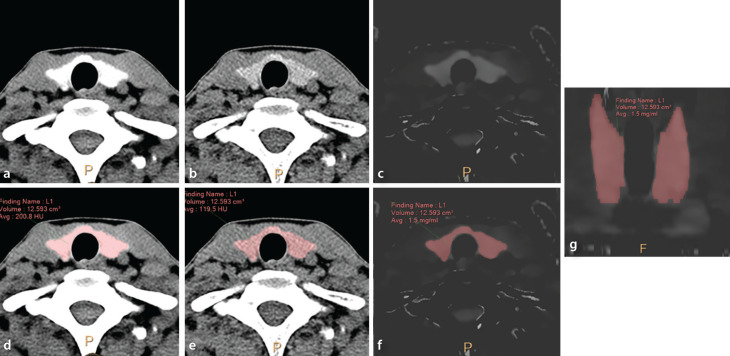

Methods: We retrospectively included patients who underwent neck CT examination between September 2016 and August 2021 using a dual-layer DECT scanner (120 kilovolt peak) for preoperative thyroid imaging. We performed volumetric IC measurements at the thyroid parenchyma on the additional iodine map generated from non-contrast images. We then compared the mean IC of thyroid parenchyma based on thyroid hormonal status (hypothyroid, euthyroid, and hyperthyroid) and diffuse thyroid disease (DTD). Additionally, we determined the accuracy of iodine quantification with our site-specific DECT acquisition protocol using a GammexTM phantom containing seven iodine inserts with different ICs ranging from 2 to 20 mgI/mL.

Results: Among the 578 patients (M:F: 87:491, age: 48.6 ± 11.7 years) who were finally selected, the mean thyroid parenchymal ICs was the lowest in the hyperthyroid group, followed by the hypothyroid group, and then the euthyroid group (0.68 ± 0.37, n = 44 vs. 1.13 ± 0.42, n = 61 vs. 1.32 ± 0.43, n = 473, P < 0.01, respectively). In the patients with euthyroidism, the mean parenchymal IC was already lower in the patients with pathologically proven DTD than in those without DTD (1.22 ± 0.44 mgI/mL vs. 1.45 ± 0.37 mgI/mL, P < 0.01). Based on the phantom study, the median percentage deviations from the expected values were 5.1% for ICs of 2-20 mgI/mL.